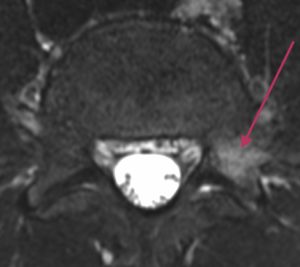

Lannerangan poikkileikkaus 2

Toinen poikkileikkaustaso eri nikamavälistä.